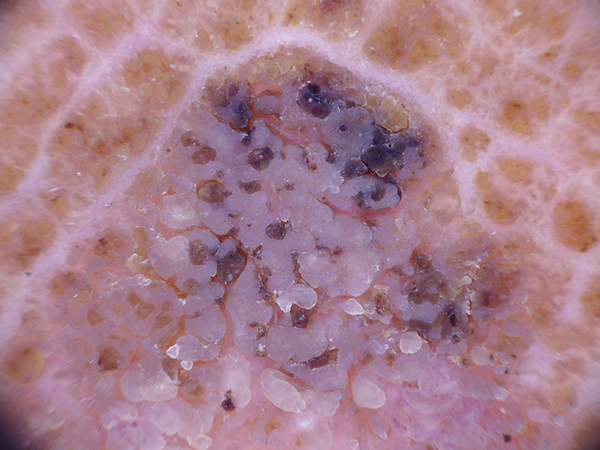

Benign keratosis-like lesions